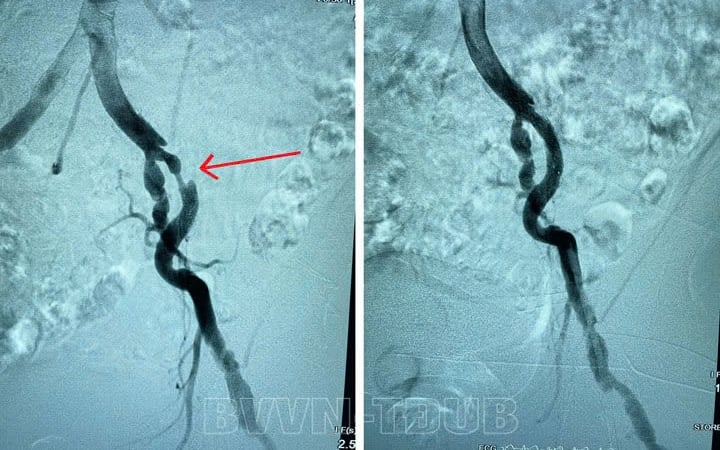

Ngay khi tiếp nhận người bệnh, tiến hành siêu âm mạch các bác sĩ phát hiện người bệnh có tình trạng hẹp, tắc động mạch chi dưới. Hình ảnh chụp mạch số hóa xóa nền DSA cho thấy tình trạng hẹp động mạch chậu ngoài bên trái, vị trí hẹp nhiều nhất là 90%.

Hình ảnh hẹp tắc mạch của người bệnh trước và sau khi can thiệp(vị trí mũi tên chỉ) Nhận định đây là trường hợp bệnh nặng, phức tạp, xơ vữa gây chít hẹp động mạch với nguy cơ tiến triển nặng, bác sĩ tiến hành hội chẩn và quyết định thực hiện phương án tối ưu nhất bằng can thiệp nong bóng và đặt stent động mạch chậu cho người bệnh.

Chụp mạch đánh giá sau can thiệp cho thấy các vị hẹp, tắc được tái thông, người bệnh hết tình trạng đau nhức, tê bì chân trái.